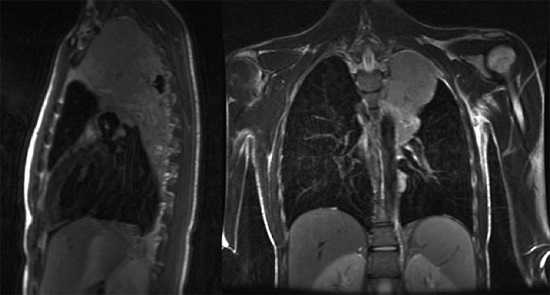

КТ с контрастированием (мягкотканное окно), первое из шести аксиальных изображений: нормальные структуры грудной стенки. На первом срезе визуализируются мышцы грудной стенки в надключичной области. КТ с контрастированием, аксиальный срез через верхушки легких: визуализированные структуры включают нормальные подключичные и подмышечные сосуды. КТ с контрастированием, аксиальный срез через медиальные отделы ключиц: мышцы, прикрепляющиеся к лопатке. КТ с контрастированием, аксиальный срез на уровне ветвей дуги аорты. КТ с контрастированием, аксиальный срез на уровне дуги. КТ с контрастированием, аксиальный срез через субкаринальную область. На первом из шести аксиальных Т1-взвешенных МР-томограмм представлены нормальные структуры грудной стенки. Первый срез выполнен через надключичную область. МРТ, аксиальное Т1-ВИ через верхушки легких. МРТ, аксиальное Т1-ВИ на уровне дуги аорты. МРТ, аксиальное Т1-ВИ на уровне аортолегочного окна. МРТ, аксиальное Т1-ВИ через легочные артерии. МРТ, аксиальное Т1-ВИ через нижние доли легких и нижние легочные вены. КТ с контрастированием (костное окно), первое из шести корональных изображений спереди назад: мышцы грудной стенки в норме. Первый срез получен на уровне грудино-ключичных суставов. КТ с контрастированием, корональный срез на уровне легочных артерий. КТ с контрастированием, корональный срез на уровне киля трахеи. КТ с контрастированием, корональный срез на уровне нисходящего отдела грудной аорты. КТ с контрастированием, корональный срез на уровне грудного отдела позвоночного канала. КТ с контрастированием, корональный срез на уровне задних отрезков ребер и остистых отростков. Первая из шести корональных Т1-взвешенных МР-томограмм: нормальные структуры грудной стенки (спереди назад). Первый срез получен через медиальные отделы ключиц. МРТ, корональное Т1-ВИ на уровне подключичной вены. МРТ, корональное Т1-ВИ на уровне подключичных артерий и переднего отдела плечевого сплетения. МРТ, аксиальное Т1-ВИ через плечевое сплетение и превертебральные структуры. МРТ, аксиальное Т1-ВИ через грудной отдел позвоночного канала. МРТ, аксиальное Т1-ВИ через задние отрезки ребер. Рентгенограмма, фокусированный вид, заднепередняя проекция: частично визуализируемая рукоятка грудины, грудино-ключичные суставы, характерный ход первых ребер и их сочленения с латеральными краями рукоятки грудины. КТ с контрастированием (костное окно), сагиттальный срез: у мужчины 25 лет определяется нормальная анатомия грудины, визуализированы рукоятка, тело и мечевидный отросток.